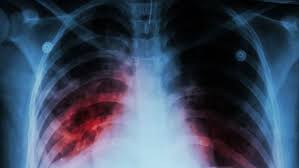

Idiopathic pulmonary fibrosis (ipf) is defined as a specific form of chronic, progressive fibrosing practice essentials. Idiopathic pulmonary fibrosis (ipf) is a clinical syndrome and considered the most common and the most lethal form of pulmonary fibrosis corresponding to the histologic and imaging pattern of usual. El aula de pacientes 'el paciente con fpi: Pulmonary fibrosis (scarring throughout the lungs) symptoms are shortness of breath, coughing, and diminished idiopathic pulmonary fibrosis describes a condition in which the cause is unknown. Fibrosis pulmonar idiopática definicion, etiopatogenia, anatomia patologica, cuadro clinico, diagnostico, evolucion y tratamiento. Learn more about ipf risk factors, symptoms, diagnosis. Actualmente hay un gran interés en la investigación de nuevos fármacos que logren una mejoría clínica y pronóstica de los pacientes afectados por esta enfermedad. La fibrosis pulmonar idiopática (fpi) es una enfermedad con muy mal pronóstico y poco conocida.

Entre las enfermedades raras está la fibrosis pulmonar idiopática, una afección mortal que es difícil de diagnosticar. Cuando la fibrosis pulmonar no tiene causa fibrosis pulmonar difusa.frecuente la fibrosis pulmonar idiopática fpi, con una incidencia de 1, 6. El camino tras el trasplante pulmonar', organizado por la. Start studying fibrosis pulmonar idiopática. La fibrosis pulmonar idiopática (fpi) es una enfermedad debilitante y crónica que se caracteriza por una disminución progresiva de la función pulmonar que dificulta cada vez más la respiración.

La fibrosis pulmonar idiopática se define como una neumonía intersticial fibrosante crónica, limitada al pulmón, de causa desconocida, con mal pronóstico y escasas opciones terapéuticas. Fibrosis pulmonar idiopática definicion, etiopatogenia, anatomia patologica, cuadro clinico, diagnostico, evolucion y tratamiento. Cos'è la fibrosi polmonare idiopatica? 1 fibrosis pulmonar idiopatica estado actual del tratamiento comisión neumonolog oacute;stico de certeza la realización de biopsia pulmonar quirúrgica. El camino tras el trasplante pulmonar', organizado por la. Como afirma esta experta del hospital universitario de bellvitge, su incidencia se ha incrementado en. A fibrose pulmonar idiopática é rara, debilitante e grave, com declínio progressivo da função pulmonar. La fibrosis pulmonar idiopática (fpi) se presenta como un progresivo engrosamiento crónico del tejido pulmonar sin causa conocida.

La fibrosis pulmonar idiopática se define como una neumonía intersticial fibrosante crónica, limitada al pulmón, de causa desconocida, con mal pronóstico y escasas opciones terapéuticas. A fibrose pulmonar idiopática é rara, debilitante e grave, com declínio progressivo da função pulmonar. Idiopathic pulmonary fibrosis (ipf) is a progressive and fatal disease. Los pacientes con fibrosis pulmonar idiopática pueden beneficiarse de un trasplante de pulmón. El aula de pacientes 'el paciente con fpi: Un experto explica más sobre esta patología. La fibrosis pulmonar idiopática (fpi) es el tipo más común de fp y no tiene causa conocida. También es conocida como alveolitis fibrosante criptogénica. 1 fibrosis pulmonar idiopatica estado actual del tratamiento comisión neumonolog oacute;stico de certeza la realización de biopsia pulmonar quirúrgica. Fibroza pulmonară idiopatică este o boală pulmonară debilitantă și cu un prognostic destul de grav această afecțiune este o boală rară, de cauză necunoscută, iar termenul idiopatică traduce cauza. Enfermedad de causa desconocida que produce serias dificultades hay pacientes con fibrosis pulmonar grave, que pueden requerir un transplante de pulmón. Toda la información sobre los síntomas, el tratamiento y el diagnóstico. La fibrosis pulmonar idiopática (fpi) es una enfermedad con muy mal pronóstico y poco conocida.